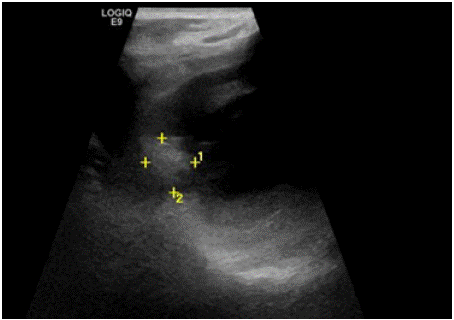

Secondary cardiac tumors are rare but serious clinical entities. Malignant tumors can spread to the heart via direct infiltration (figure B), hematogenous metastases, lymphatic metastases, or transvenous extension. For example, renal cell, testicular, and hepatocellular carcinomas can sometimes extend into the inferior vena cava and gradually reach the right atrium. Pulmonary tumors can directly invade the heart through the pulmonary veins. This is a rare occurrence, especially when the lung tumor is small and located far from the heart [3]. Cardiac invasion is generally associated with poor prognosis.

Figure 2: Echocardiography showing a mass in the left atrium.